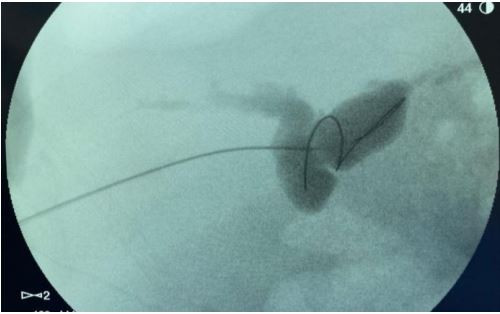

Realizada Colangiopancreatografia Retrógrada Endoscópica (CPRE) com achado abaixo, onde se observa dificuldade de passagem de fio guia devido tortuosidade de colédoco do receptor:

Frente ao presente caso, a melhor conduta é: